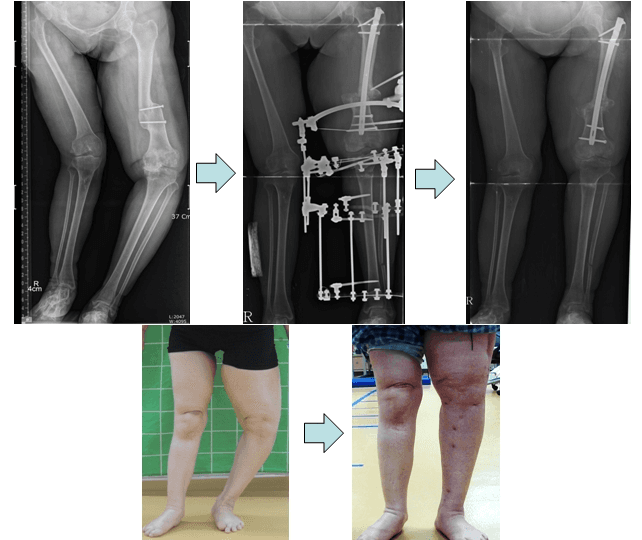

Correction of left lower limb deformity in poliomyelitis.